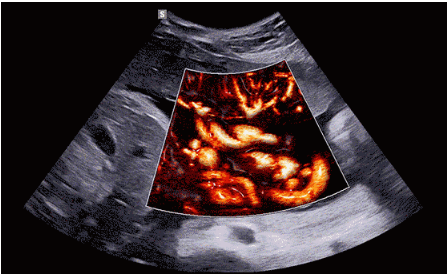

CrystalLive?是三星最新的超聲成像引擎,同時增強(qiáng)了2D圖像處理能力、3D渲染能力和彩色信號處理能力,能夠在復(fù)雜情況下提供出色的圖像性能,具備檢測外周血管、微循環(huán)血流的能力。

3D/4D成像方面,Hera i 10通過結(jié)合先進(jìn)的圖像渲染技術(shù),著重加強(qiáng)了邊緣和小結(jié)構(gòu)的可視化能力。